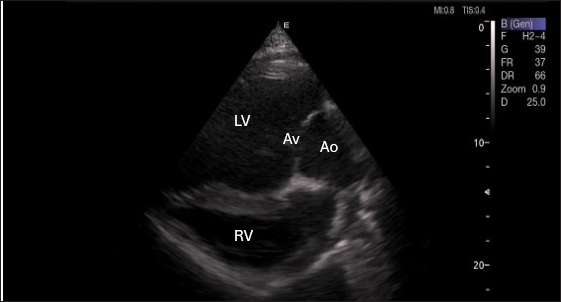

Right parasternal ultrasonography

By positioning the probe perpendicularly in the fourth intercostal space or longitudinally in the fifth space with a little clockwise rotation, the interventricular septum, ventricles, and atria could be observed in the caudal long-axis four-chamber view (Fig. 1). From this vantage point, all camels could be seen to have a left ventricle, mitral valve, interventricular septum, right ventricle, and tricuspid valve. Figure 2 shows that in the short-axis image of the cardiac ventricles obtained with a little clockwise rotation at the 4th ICS, only the right ventricle, interventricular septum, and left ventricle were visible. Here, the dimensions of all camel heart were measured in M mode. The right parasternal two-dimensional short-axis pictures of the heart’s base in the first frame were used to determine the LA/Ao ratio, by applying 2D and M mode (Figs. 3 and 4). Despite some difficulties, we successfully acquired a pulmonary image by attempting to acquire the right ventricular outflow tract for the right short axis at the level of the great vessels.

Fig. 1. Right parasternal longitudinal axis (systole) of 16 years racing camel showing Lv=left ventricle, Rv=right ventricle, Ivs=Inte3r ventricular septum, Mv=mitral valve, and Tv=tricuspid valve.